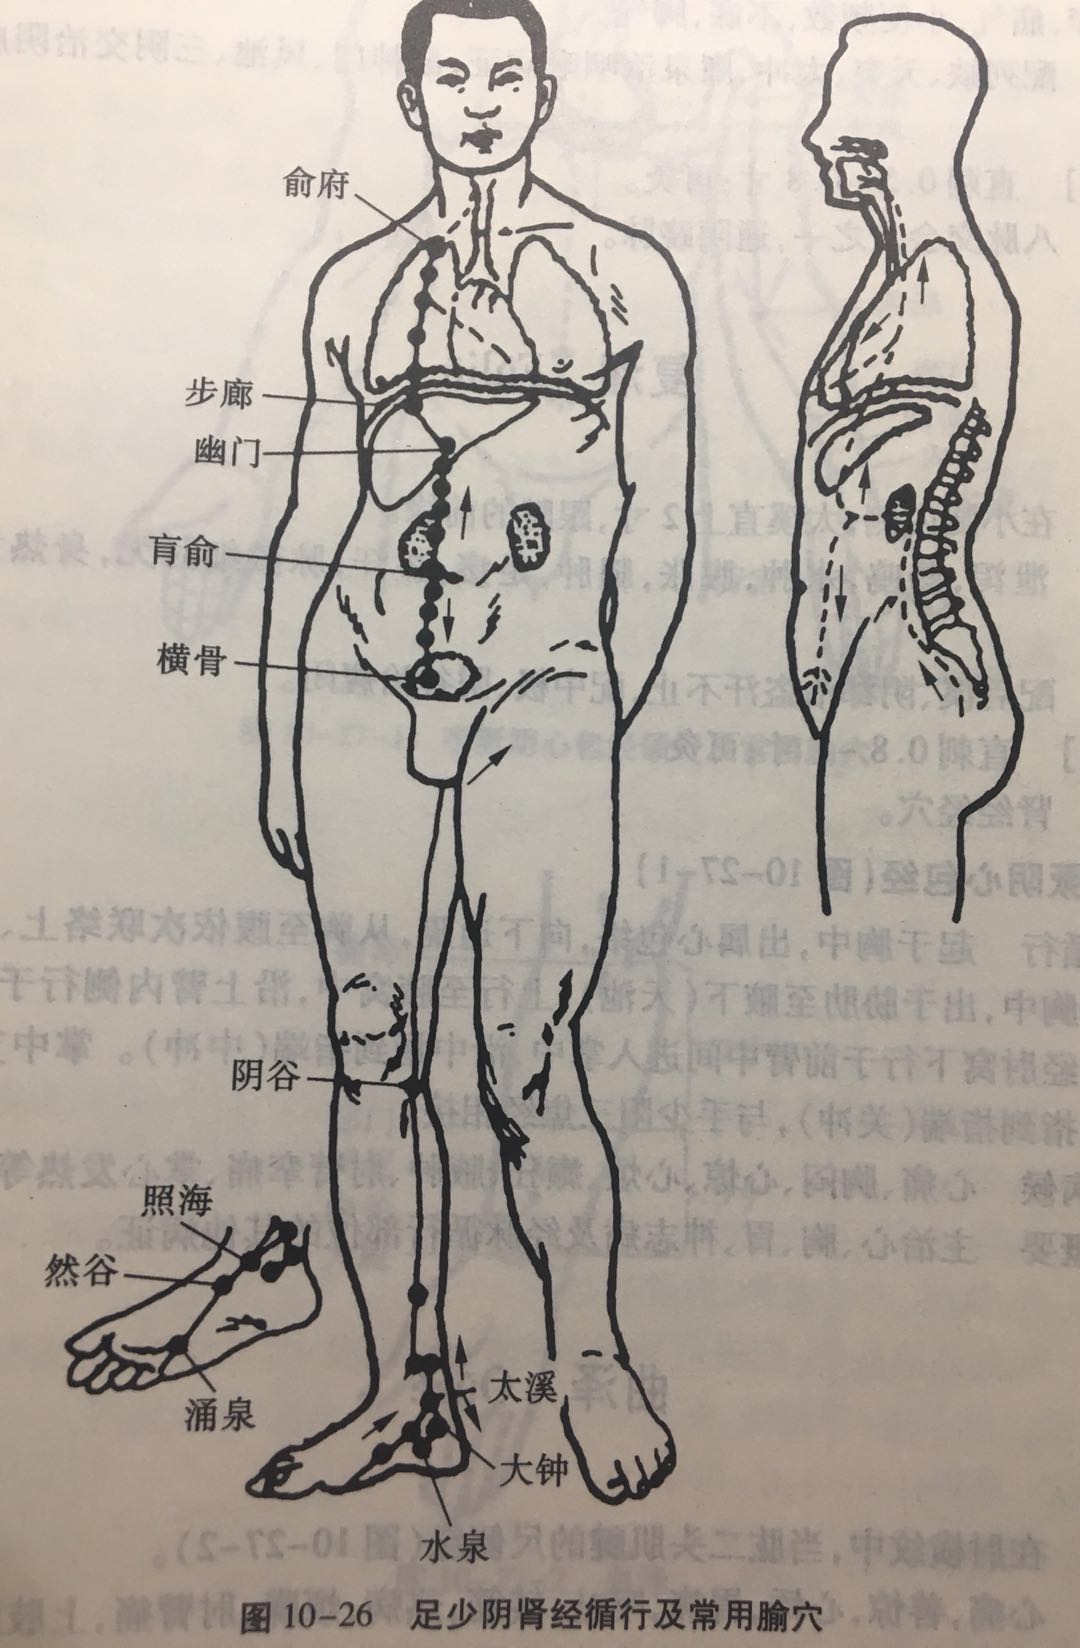

【(八)足少阴肾经(图10-26)】

1、时辰 酉时 17 ~ 19

2、歌诀 足少阴穴二十七,涌泉然谷太溪溢。大钟水泉通照海,复溜交信筑宾实。阴谷膝内跗骨后,以上从足走至膝。横骨大赫联气穴,四满中注肓(huāng)俞脐(qí)。商曲石关阴都密,通谷幽门寸半辟。折量腹上分十一,步廊神封膺灵墟。神藏彧(yù)中俞府毕。

3、经脉循行 起于足小趾之下,斜向足心(涌泉)出于舟骨粗隆下,沿内踝后向上行于腿肚内侧,经股内后缘,通过脊柱(长强)属于肾脏,联络膀胱。

肾脏部直行脉:从肾向上通过肝和横膈,进入肺中,沿着喉咙,夹于舌根部。

肺部支脉:从肺部出来,络心,流注于胸中,与手厥阴心包经相接。

4、主要病候 咳血、气喘、舌干、咽喉、肿痛、水肿、大便秘结、泄泻、腰痛、脊股内后侧痛,痿弱无力,足心热等证。

5、主治概要 主治妇科,前阴病、肾、肺、咽喉病及经脉循行部位的其他病证。

涌泉

【定位】 在足底部,卷足时足前部凹陷处,约当第 2、3 趾趾缝纹头端与足跟连线的前 1/3 与后 2/3 交点(图 10-26)。

【主治】 头顶痛,头晕,眼花,咽喉痛,舌干,失音,小便不利,大便难,小儿惊风,足心热,癫疾,霍乱转筋,昏厥。

【配伍】 配然谷治喉痹,配阴陵泉治热病夹脐急痛、胸胁满,配水沟、照海治癫痫,配太冲、百会治头项痛。

【刺灸法】 直刺 0.5 ~ 0.8 寸;可灸。

【附注】 肾经井穴。

太溪

【定位】 在足内侧,内踝后方,当内踝尖与跟腱之间的中点凹陷处。

【主治】 头痛目眩,咽喉肿痛,齿痛,耳聋,耳鸣,咳嗽,气喘,胸痛咳血,消渴,月经不调,失眠,健忘,遗精,阳痿,小便频数,腰脊痛,下肢厥冷,内踝肿痛。

【配伍】 配然谷主治热病烦心、足寒、多汗,配肾俞治肾胀,配支沟、然谷治心痛如锥刺。

【刺灸法】 直刺 0.5 ~ 0.8 寸;可灸。

【附注】 肾经腧穴、原穴。

照海

【定位】 在足内侧,内踝尖下方凹陷处。

【主治】 咽喉干燥,痫证,失眠,嗜卧,惊恐不宁,目赤肿痛,月经不调,痛经,赤白带下,阴挺,阴痒,疝气,小便频数,不寐,脚气。

【配伍】 配列缺、天突、太冲、廉泉治咽喉病证,配神门、风池、三阴交治阴虚火旺之失眠症。

【刺灸法】 直刺 0.5 ~ 0.8 寸;可灸。

【附注】 八脉交会穴之一,通阴跷脉。

复溜

【定位】 在小腿内侧,太溪直上 2 寸,跟腱的前缘。

【主治】 泄泻,肠鸣,水肿,腹胀,腿肿,足痿,盗汗,脉微细时无,身热无汗,腰脊强痛。

【配伍】 配后溪、阴郗治盗汗不止,配中极、阴谷治癃闭。

【刺灸法】 直刺 0.8 ~ 1 寸;可灸。

【附注】 肾经经穴。